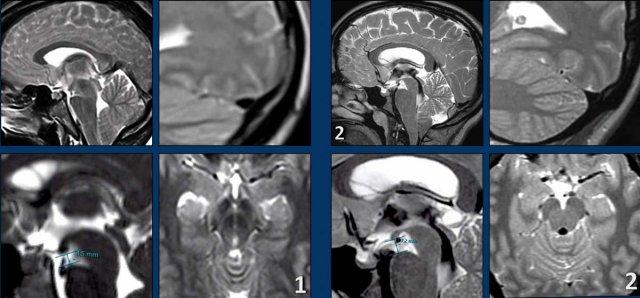

SIH và Dị dạng Chiari type I

Mặc dù SIH và dị dạng Chiari type I (CM1) là hai bệnh lý hoàn toàn khác nhau, cả hai đều có thể biểu hiện với đau đầu mạn tính và hạnh nhân tiểu não tụt thấp.

Ở bệnh nhân SIH, điều này có thể dẫn đến chẩn đoán nhầm thành CM1.

Hãy nghiên cứu các hình ảnh trước.

Cả hai bệnh nhân đều là phụ nữ trẻ với đau đầu mạn tính.

Bệnh nhân nào mắc SIH và bệnh nhân nào mắc CM1?

Hình ảnh

- Hạnh nhân tiểu não tụt thấp

Dấu hiệu không thật sự rõ ràng, một phần do có xảo ảnh chuyển động, nhưng hình dạng thân não không bình thường và có vẻ khoảng cách giữa cầu não và thể vú bị rút ngắn.

Có thể cũng có một số dấu hiệu ứ trệ tĩnh mạch. - Ngoài hạnh nhân tiểu não tụt thấp, hình ảnh trông bình thường.

Tiếp tục với các hình ảnh bổ sung……

- Bốn hình ảnh bên trái cho thấy các dấu hiệu điển hình của SIH với bờ lồi của xoang ngang, khoảng cách ngắn giữa thể vú và cầu não, và hình ảnh trung não bị võng xuống.

- Các hình ảnh bên phải không cho thấy các dấu hiệu này.

Bệnh nhân SIH đã được điều trị bốn lần bằng vá máu mù và đạt kết quả thành công.

Bệnh nhân Chiari type I đã được phẫu thuật giải ép vùng sọ-cổ và đạt kết quả tốt.

Đây là trách nhiệm của chúng ta với tư cách là bác sĩ chẩn đoán hình ảnh: giúp bệnh nhân SIH tránh khỏi việc bị điều trị nhầm như bệnh nhân Chiari type I.